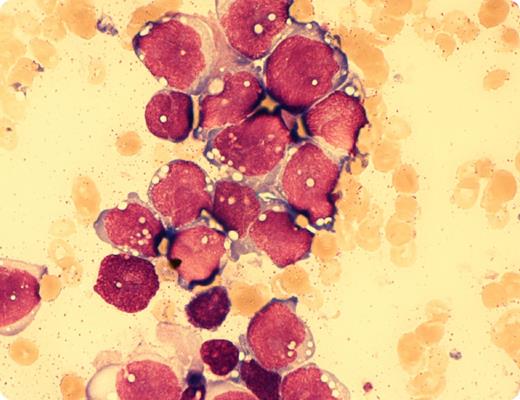

In March 2012, a 31-year-old male patient was diagnosed with alveolar rhabdomyosarcoma (ARMS) manifesting within the left sinus maxillaris with local lymphonodular metastases. No further metastases could be found by positron emission tomography–magnetic resonance imaging. He was treated by neo-adjuvant chemotherapy and consecutive radical endonasal resection and reconstruction in July 2012. In November 2012, he developed severe grade IV pancytopenia. Bone marrow aspiration revealed total bone marrow infiltration by cells with heavily vacuolated bluish cytoplasm similar to myelo-/lymphoblasts (magnification, ×100; May-Giemsa-Grünwald stain). Normal hematopoietic elements were absent. Immunohistochemistry in trephine biopsy showed a high expression of desmin. The patient received 5 cycles of palliative chemotherapy. The blood counts improved significantly with normal leukocyte and thrombocyte count. However, after 4 cycles of chemotherapy, bone marrow biopsy revealed 60% infiltration by the rhabdomyosarcoma.